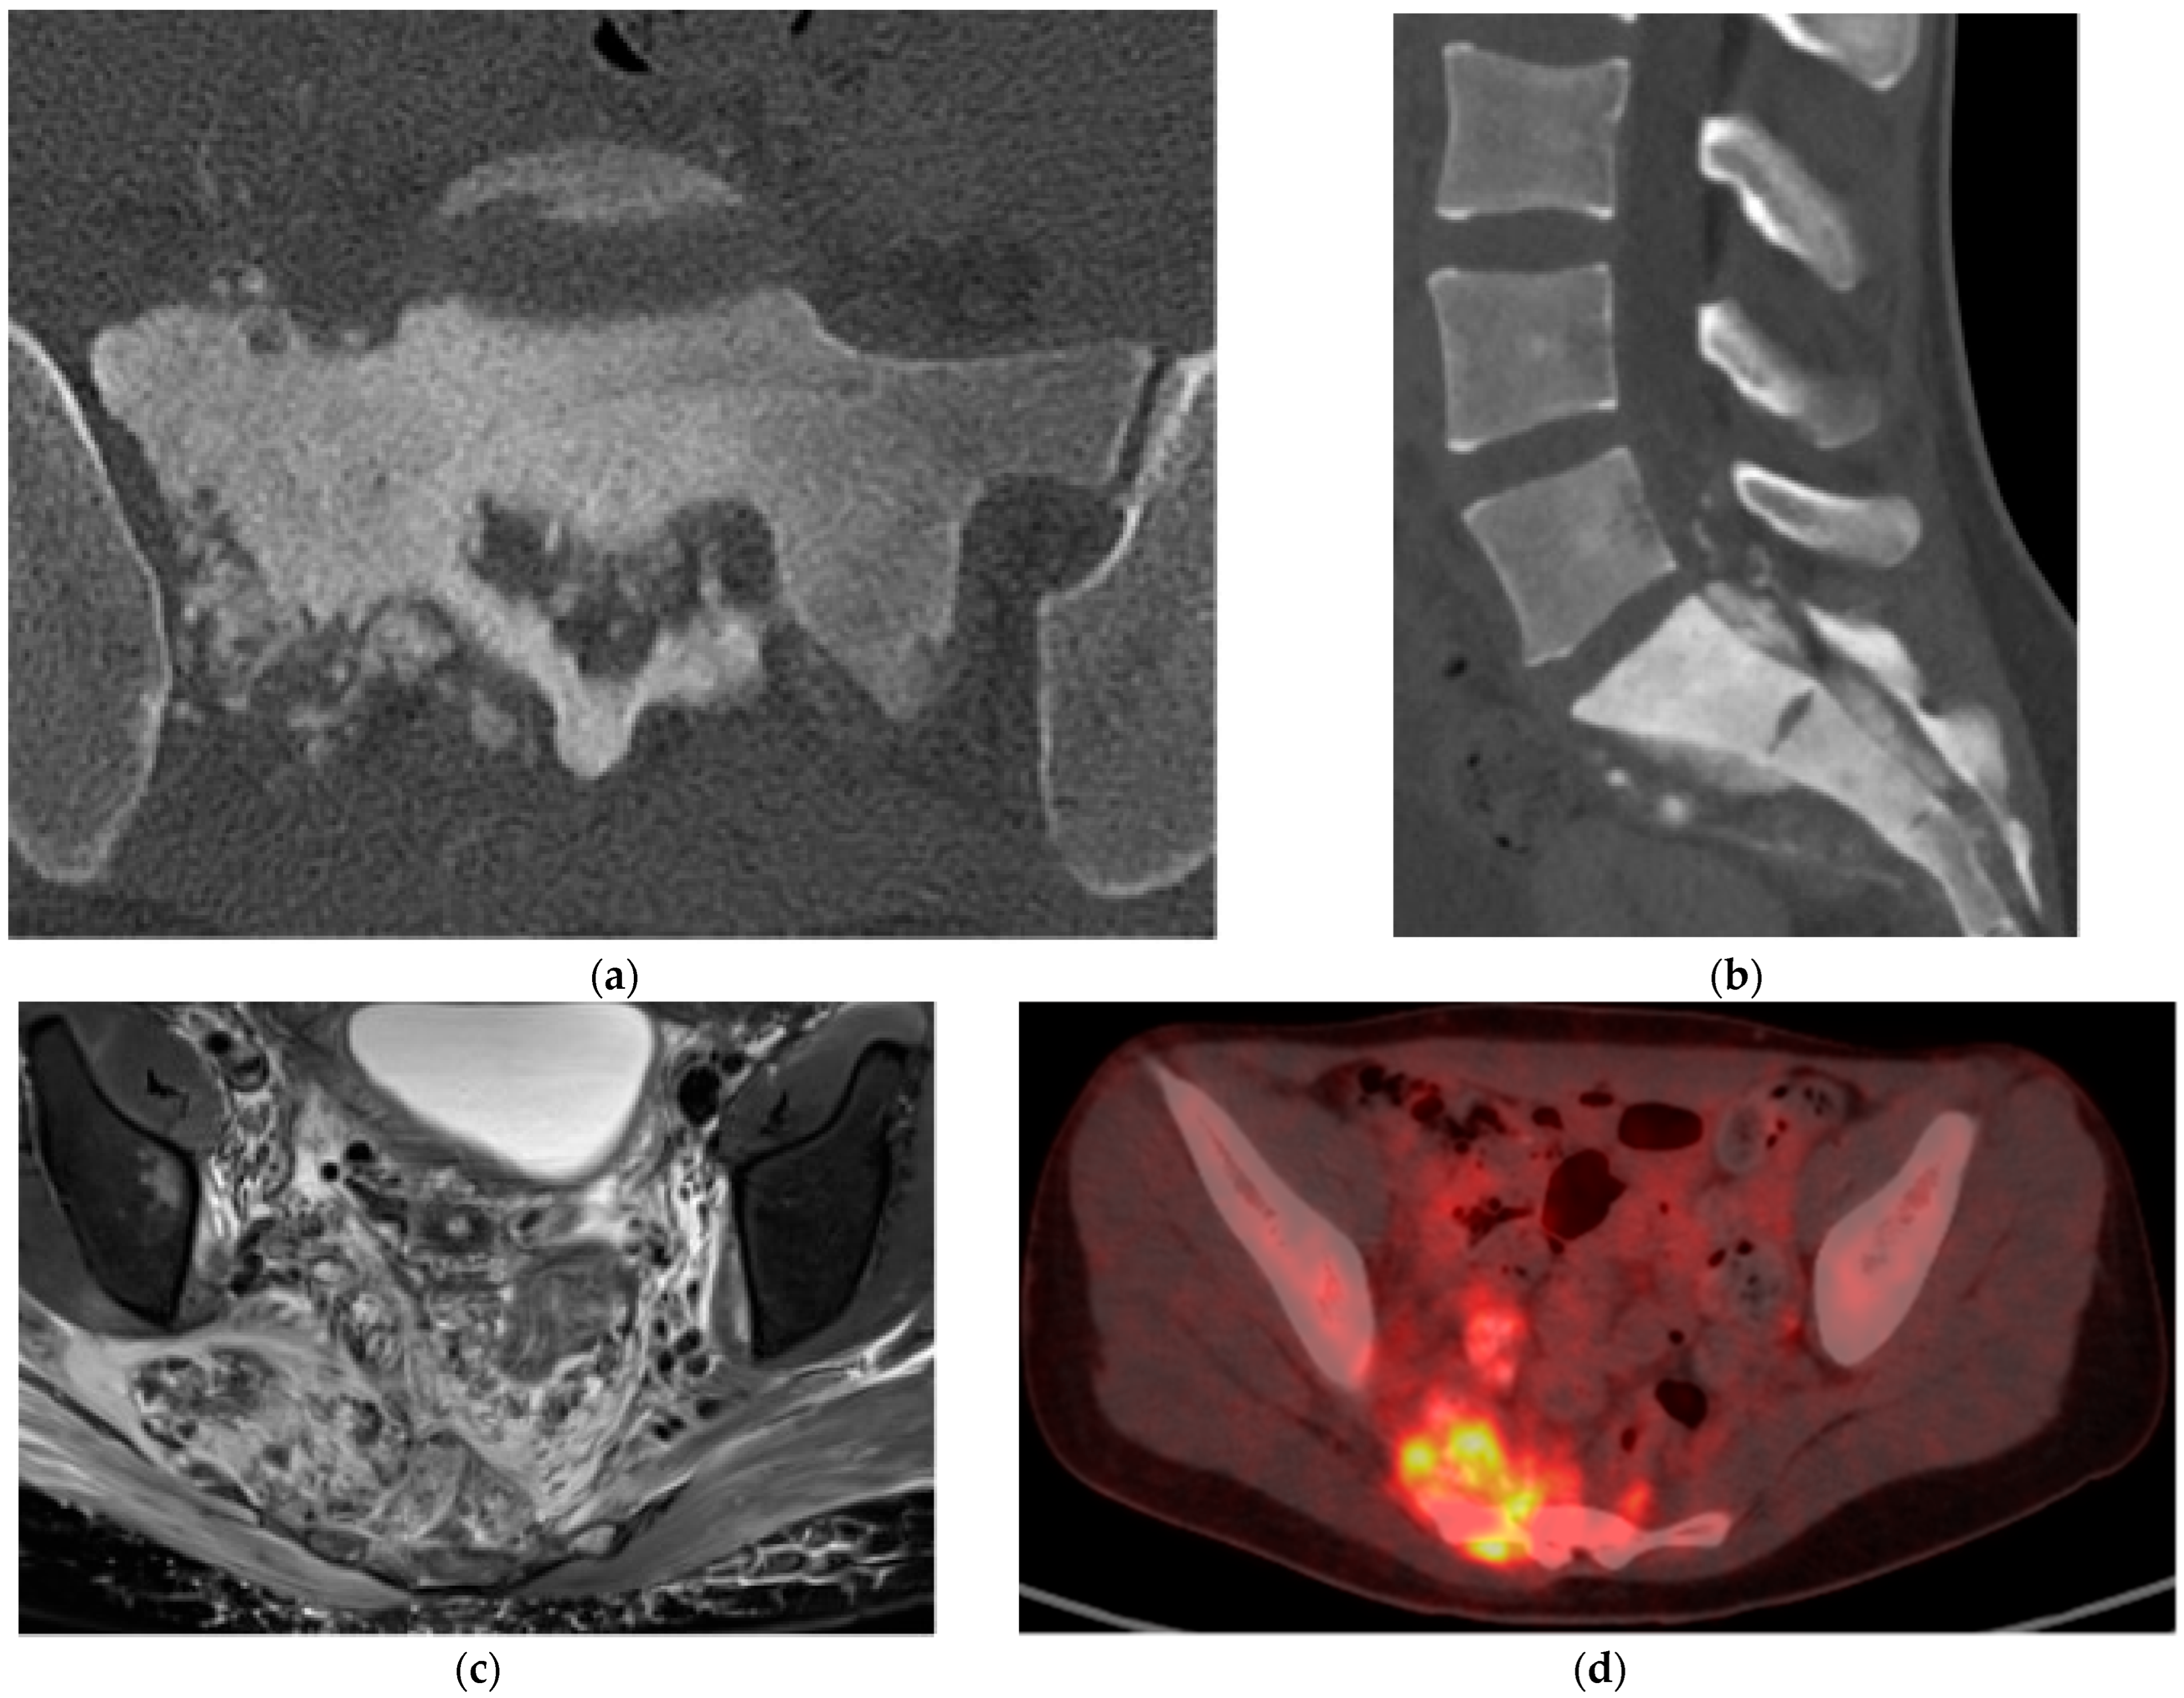

2.3.2. Chordoma